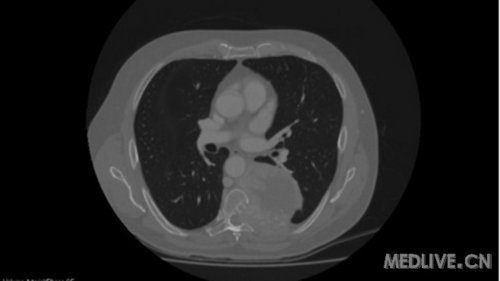

TitleBig, hypervascular paraspinal ganglioma, eroding thoracic vertebrae and ribs

大的富含血管的脊椎旁神经节瘤,侵袭胸椎和肋骨

Description: CT scan image of a huge paraspinal ganglioma extending from T4 to T9 and eroding T7 and T8 vertebrae and ribs, in close proximity to aorta and left main bronchus but not invading them.This paraganglioma was found to be hypervascular on spinal angiography.

CT扫描图像,一个巨大的脊椎旁神经节瘤,从T4到T8脊椎,侵袭了T7、T8脊椎和肋骨,非常接近主动脉和左主支气管但并未侵犯,脊髓血管造影发现这个神经节瘤富含血管。

3. Paraspinal ganglioma, Sagital CT scan

脊椎旁神经节瘤 CT矢状面扫描